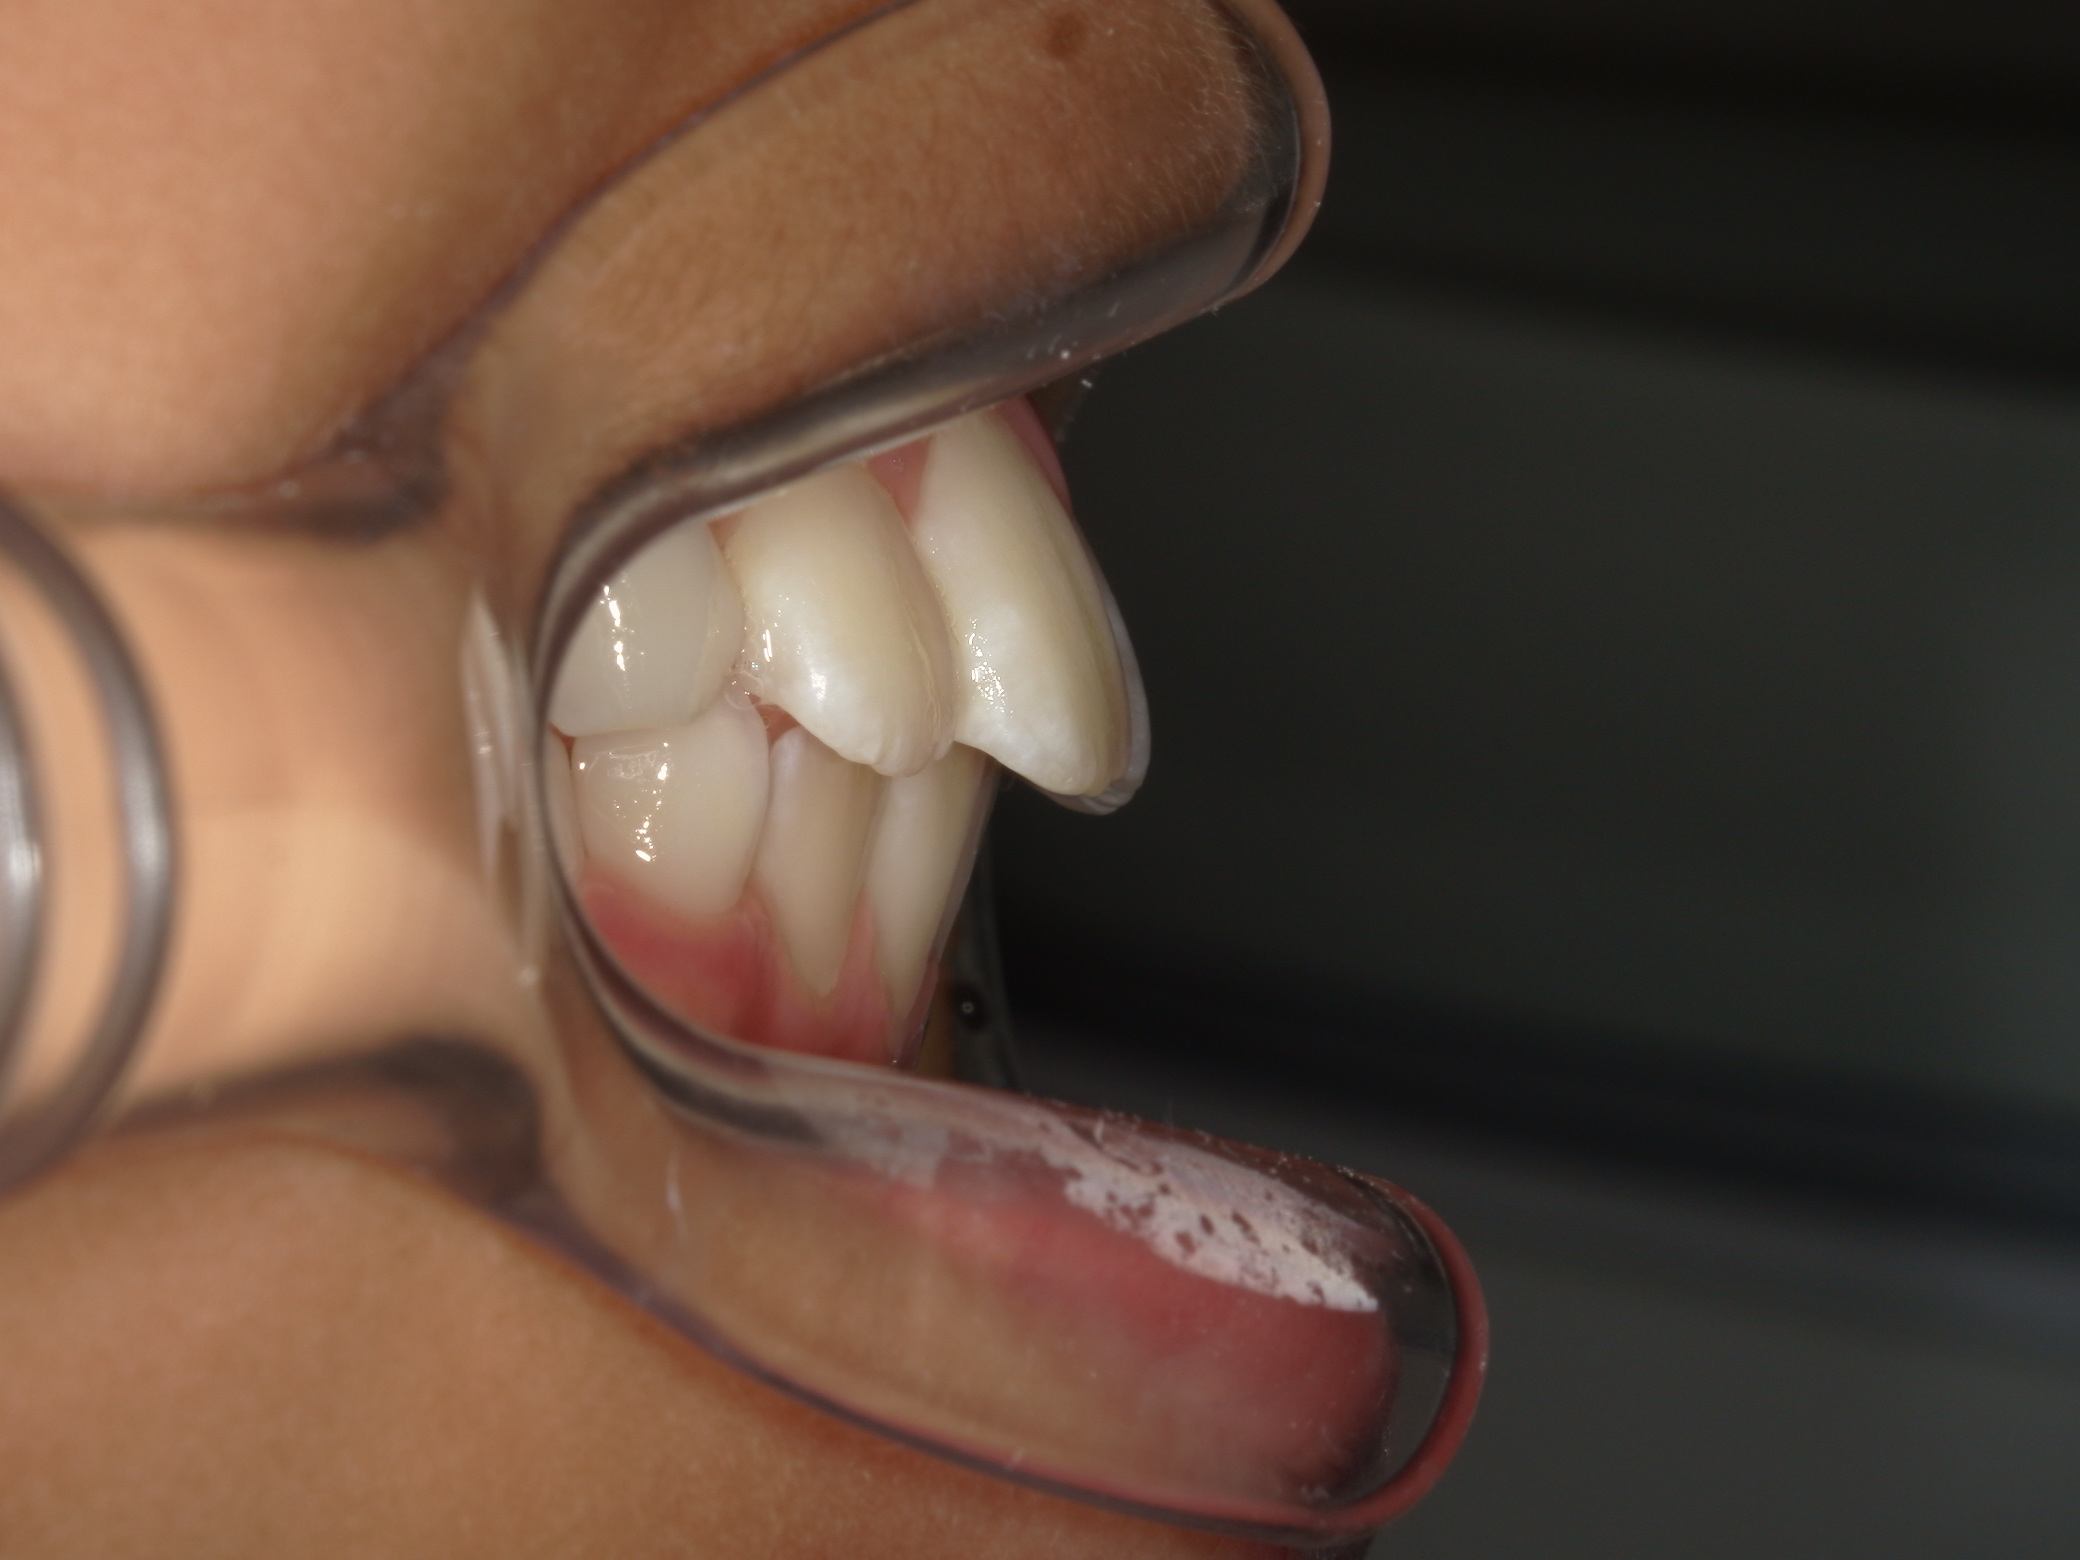

| 年齢・性別 | 11歳1ヶ月の女性 |

|---|---|

| 主訴 | 口元の突出感と歯並びが気になり、将来的な咬合状態を整える目的で来院された患者様です。 |

| 治療期間・回数 | 2年6ヶ月・25回 |

| 費用 | 720,000円 |